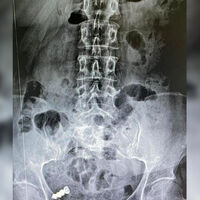

В Ростовской области врачи спасли женщину с протезом в желудке. Об этом сообщает минздрав региона.

Пациентка не сняла искусственные зубы перед сном, и, проснувшись, почувствовала недомогание.

«Утром она почувствовала неприятные ощущения в желудке и с ужасом поняла, что уснула с протезом, но сейчас его нет», – поделились в ведомстве.

Во время обследования выяснилось, что женщина проглотила протез, к этому моменту он уже находился в тонком кишечнике. Медики предположили, что инородный предмет сможет выйти естественным путем, но спустя десять дней выяснилось, что он все еще в кишечнике.

Пациентку еще раз обследовали уже в другом медучреждении и выяснили, что протез застрял в петлях тонкой кишки. Специалисты открепили мост с искусственными зубами от слизистой и провели его по кишечнику. В результате предмет извлекли. Этот случай представители минздрава назвали необычным.